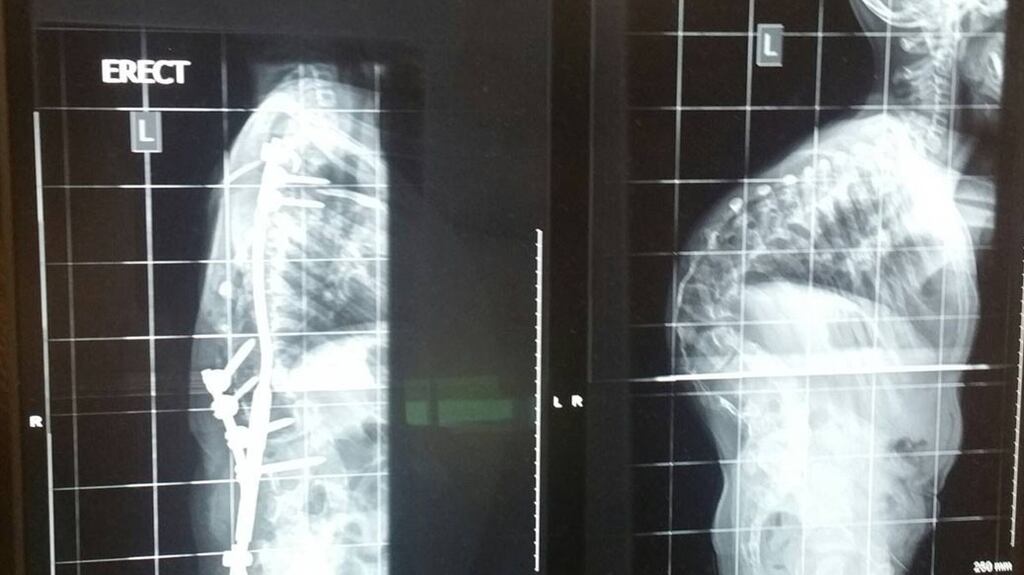

Scoliosis involves a curve of the spine which restricts movement and can interfere with breathing if it goes uncorrected.